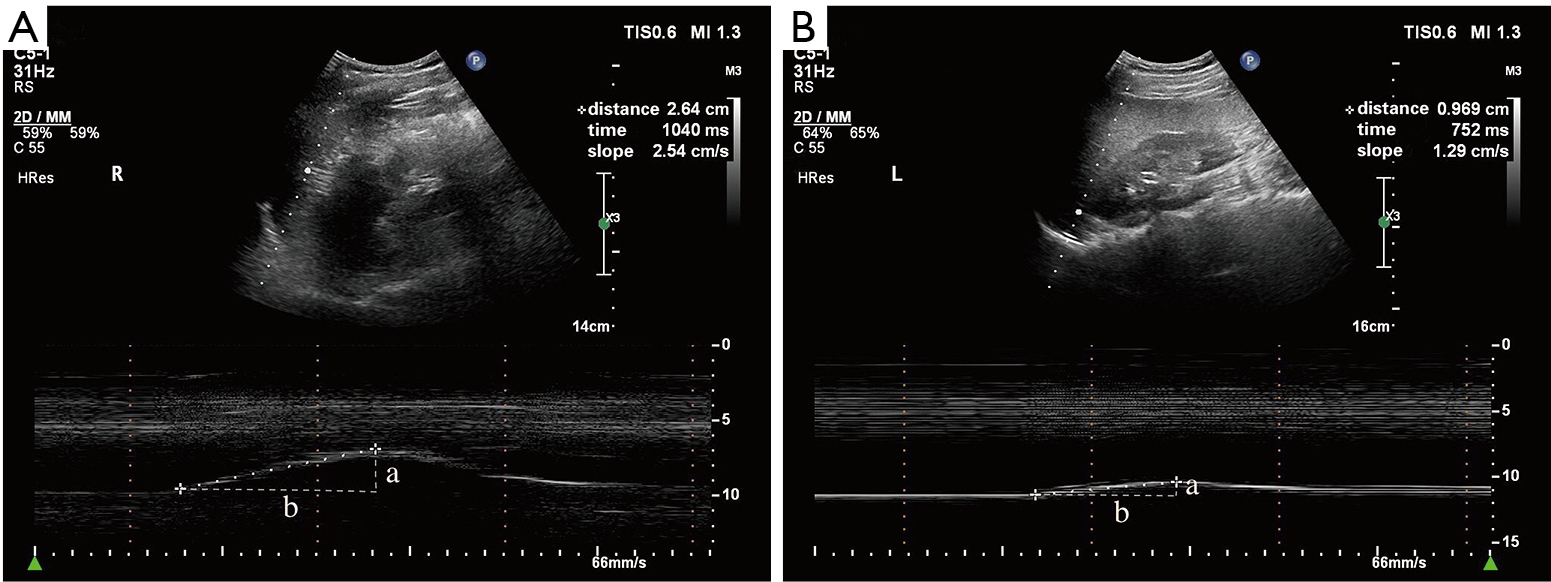

Figure I from Ultrasound assessment of ventilatorinduced diaphragmatic

Figure 1 from Using Mmode ultrasonography to assess diaphragm Diaphragmatic Excursion Does It Predict Successful Weaning From Mechanical Ventilation  2017, journal of the college of physicians and.   during weaning from mechanical ventilation and spontaneous breathing trials, both diaphragmatic excursion and diaphragmatic thickening.   measurement of diaphragmatic excursion and diaphragmatic thickening fraction predict the probability of.   diaphragmatic excursion (de) in cm was measured through ultrasound by marking liver and spleen displacement in. Does it predict successful weaning from. Diaphragmatic Excursion Does It Predict Successful Weaning From Mechanical Ventilation.